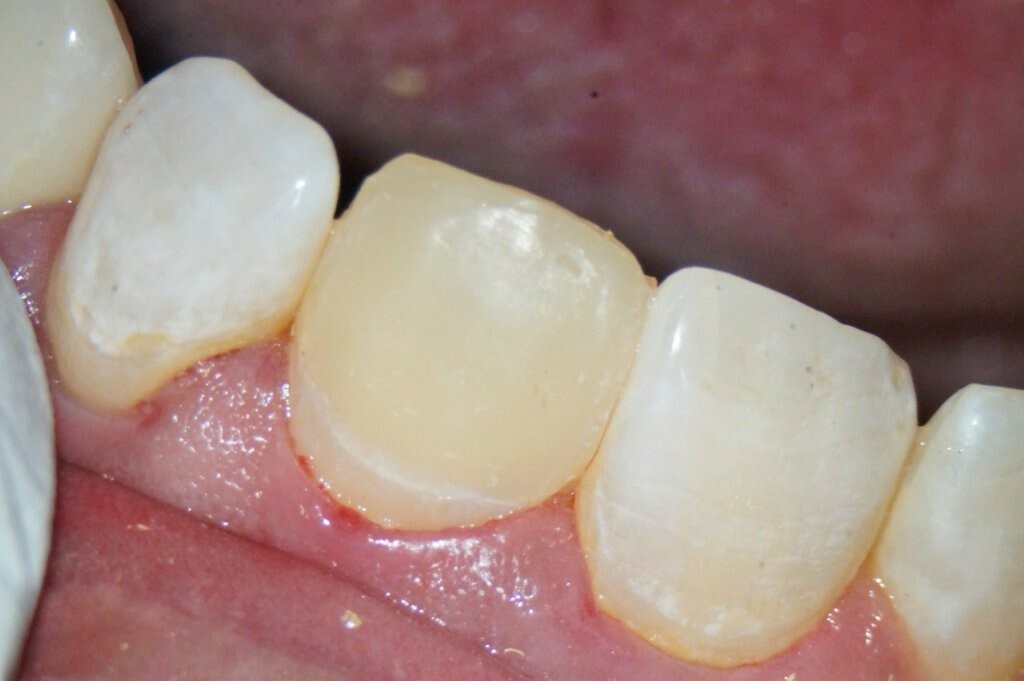

Der provisorische Aufbau erfolgte durch den Endodontologen mit vorab gefertigtem Silikonschlüssel mittels Tetric Flow und Ceram A3,5 als Abschluss der Single-Visit-Behandlung. Die endgültige Krone konnte am 12. Juni 2025 eingegliedert werden.